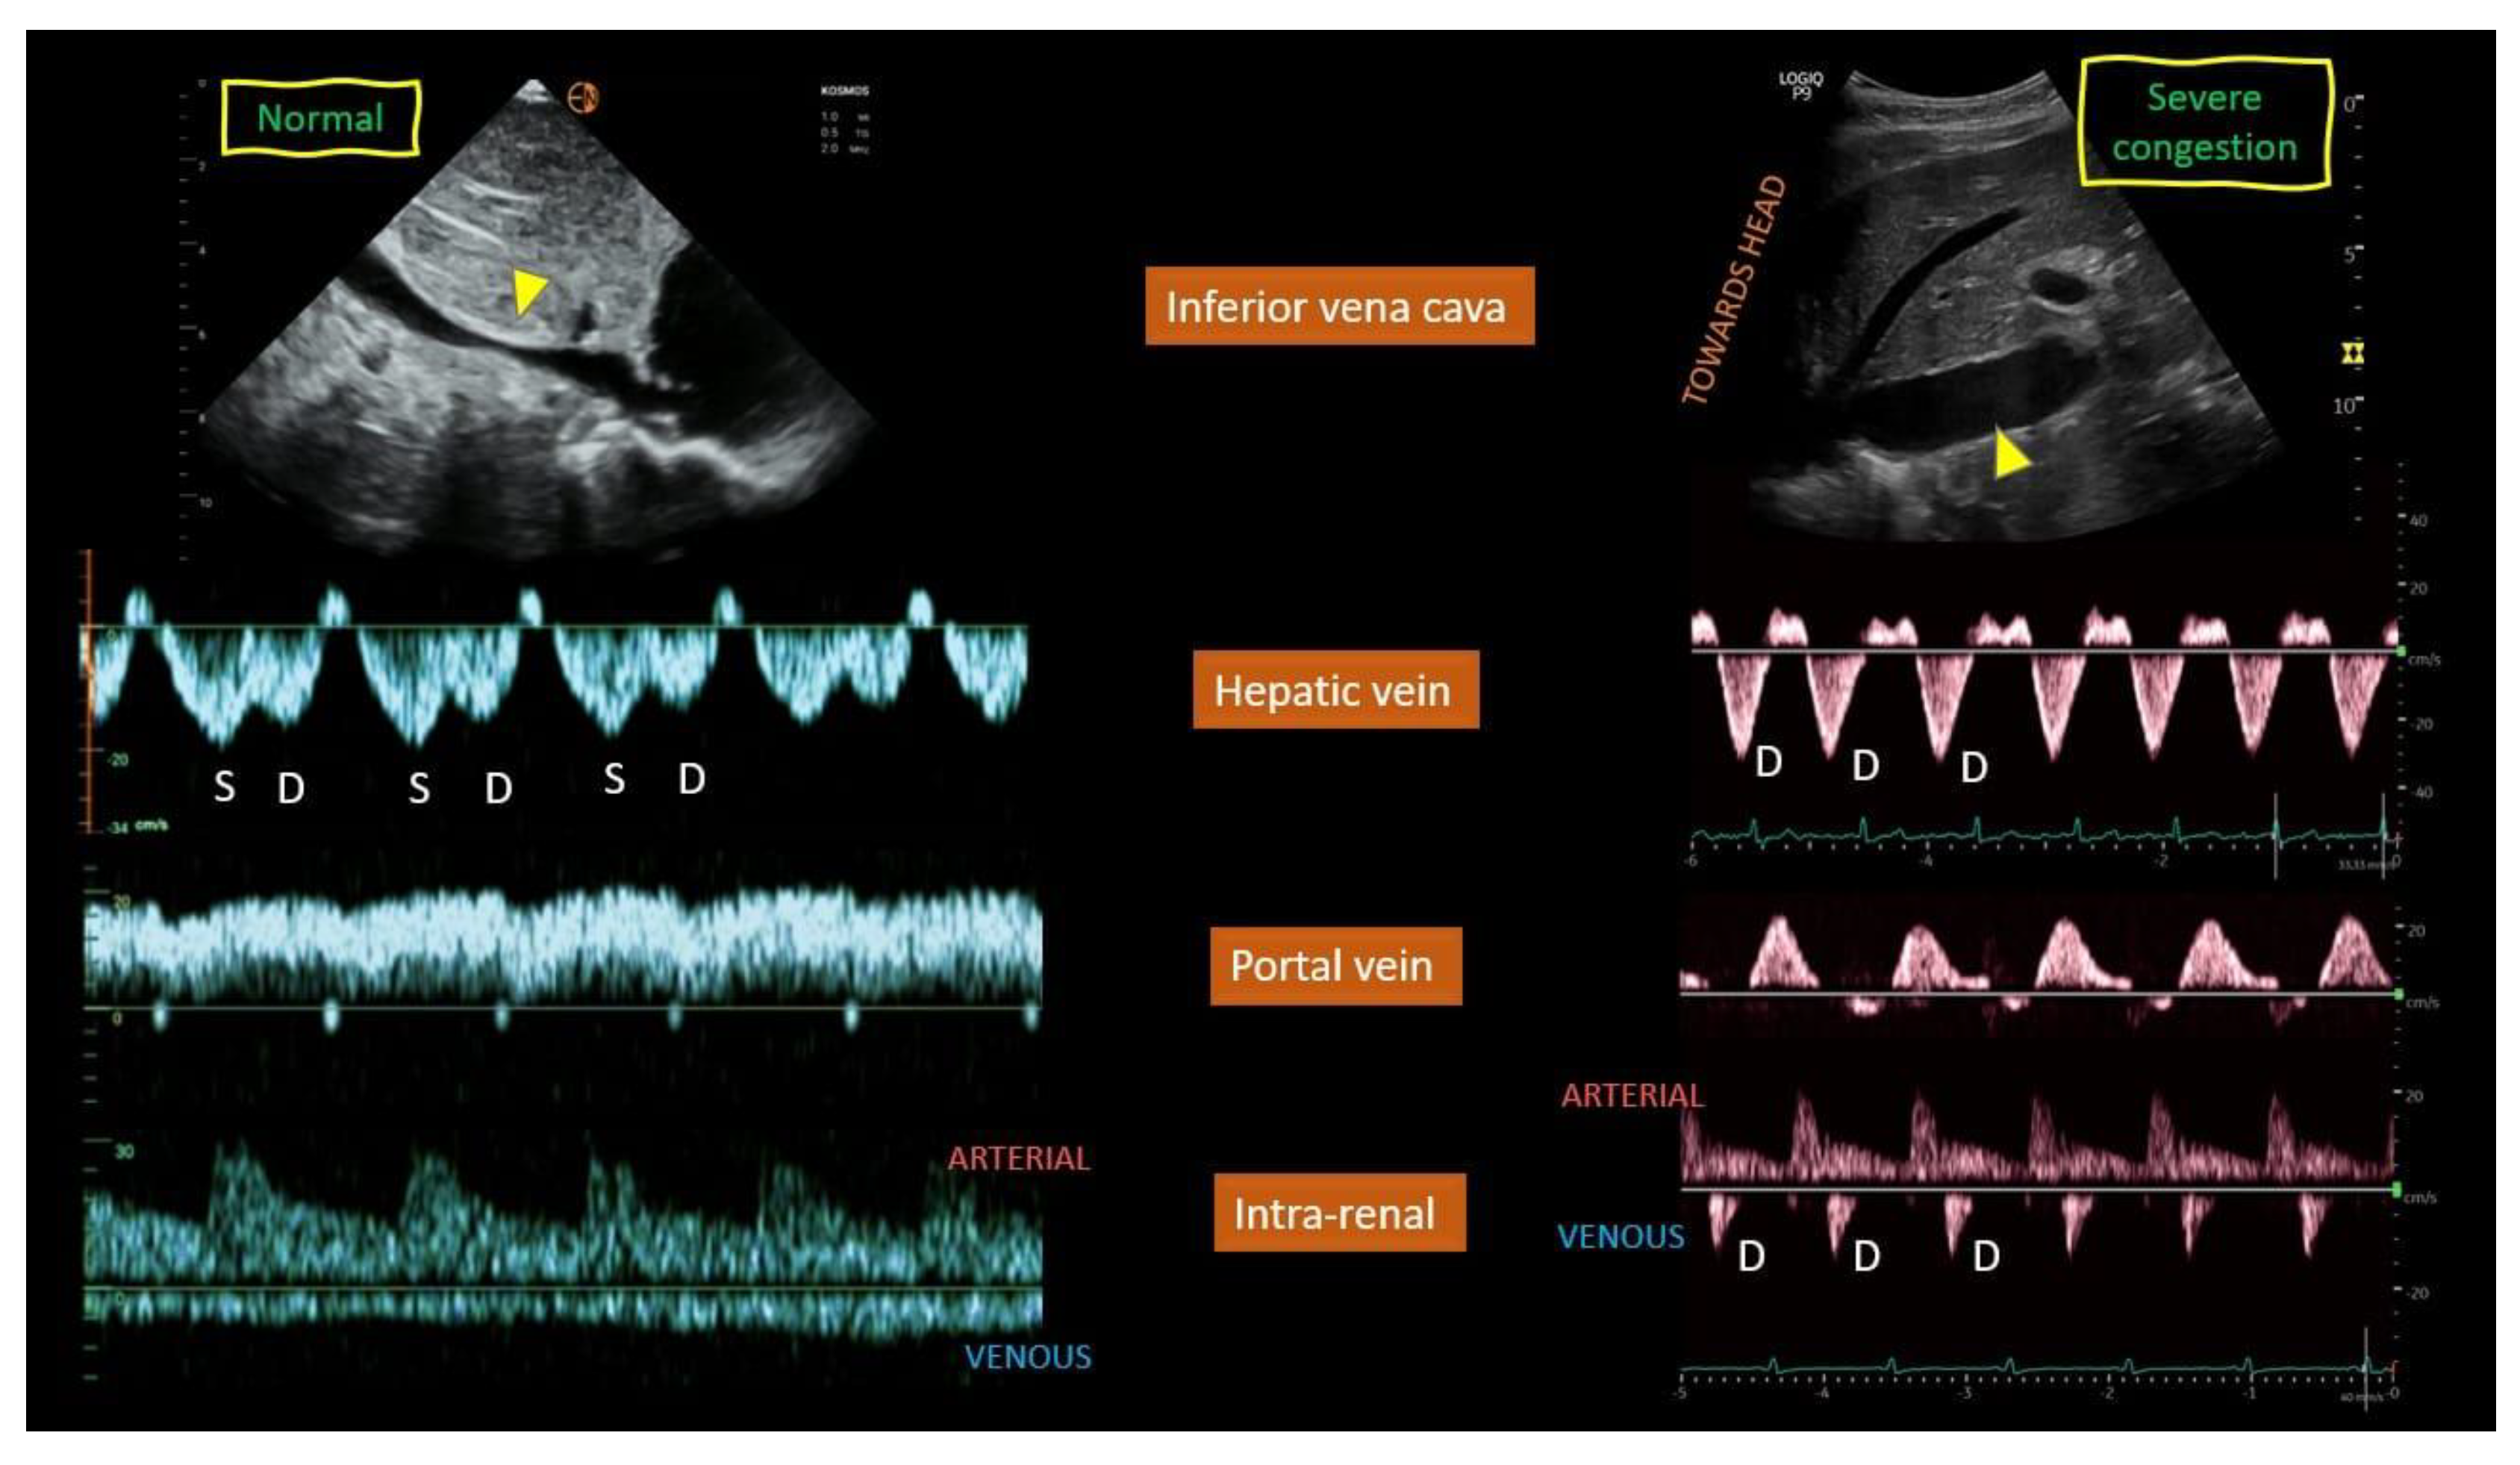

4.1.1. SYNOPSIS OF THE STUDY OF SPLANCHNIC SYSTEM CONGESTION: Venous Excess Ultrasound Score (VExUS) and EXTENDED VEXUS

| Hepatic vein Doppler | Aids in the assessment of | Same window used for assessing the | Need ECG tracing; unreliable in atrial |

| systemic venous | IVC; supplemental information (e.g., | fibrillation, right ventricular systolic | |

| congestion | right ventricular systolic function, | dysfunction, chronic PH, TR, cirrhosis | |

| constriction and tamponade); exhibits | |||

| dynamic change in response to | |||

| decongestive | |||

| treatment | |||

| Portal vein Doppler | Aids in the assessment of | Don’t need ECG; exhibits dynamic | Operator variability (Doppler sampling |

| systemic venous | change in response to decongestive | location); unreliable in athletes (e.g., | |

| congestion | treatment (pulsatility may | pulsatility without high RAP) and | |

| improve even in chronic TR) | cirrhosis (e.g., no pulsatility with high | ||

| RAP or pulsatility due to arterioportal | |||

| shunts) | |||

| Intrarenal venous | Aids in the assessment of | Simultaneous arterial Doppler allows | Technically challenging (especially when |

| Doppler | systemic venous | identification of cardiac cycle; exhibits | patients unable to hold breath); |

| congestion | dynamic change in response to | operator variability (e.g., misinterpret | |

| decongestive treatment | pulsatility of main renal vessel as renal | ||

| parenchymal vessel); change in | |||

| response to decongestive treatment | |||

| may be delayed in the presence of | |||

| interstitial edema; no available data for | |||

| patients with advanced chronic kidney | |||

| disease | |||

- Bhardwaj, V.; Vikneswaran, G.; Rola, P.; Raju, S.; Bhat, R.S.; Jayakumar, A.; Alva, A. Combination of Inferior Vena Cava Diameter, Hepatic Venous Flow, and Portal Vein Pulsatility Index: Venous Excess Ultrasound Score (VEXUS Score) in Predicting Acute Kidney Injury in Patients with Cardiorenal Syndrome: A Prospective Cohort Study. Indian J Crit Care Med 2020, 24, 783-789. [CrossRef]

- Argaiz, E.R. VExUS Nexus: Bedside Assessment of Venous Congestion. Adv Chronic Kidney Dis 2021, 28, 252-261. [CrossRef]

- Deschamps, J.; Denault, A.; Galarza, L.; Rola, P.; Ledoux-Hutchinson, L.; Huard, K.; Gebhard, C.E.; Calderone, A.; Canty, D.; Beaubien-Souligny, W. Venous Doppler to Assess Congestion: A Comprehensive Review of Current Evidence and Nomenclature. Ultrasound Med Biol 2023, 49, 3-17. [CrossRef]

- Iida, N.; Seo, Y.; Sai, S.; Machino-Ohtsuka, T.; Yamamoto, M.; Ishizu, T.; Kawakami, Y.; Aonuma, K. Clinical Implications of Intrarenal Hemodynamic Evaluation by Doppler Ultrasonography in Heart Failure. JACC Heart Fail 2016, 4, 674-682. [CrossRef]

- Beaubien-Souligny, W.; Rola, P.; Haycock, K.; Bouchard, J.; Lamarche, Y.; Spiegel, R.; Denault, A.Y. Quantifying systemic congestion with Point-Of-Care ultrasound: development of the venous excess ultrasound grading system. Ultrasound J 2020, 12, 16. [CrossRef]